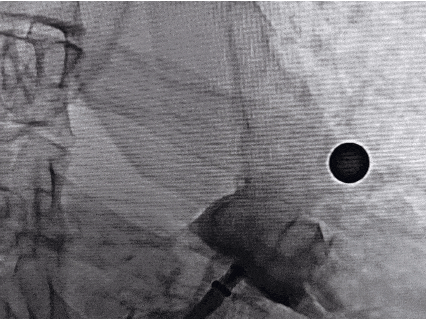

术中封堵器展开过程

导引鞘与推送鞘锁合后,退鞘缓慢展开左心耳封堵器